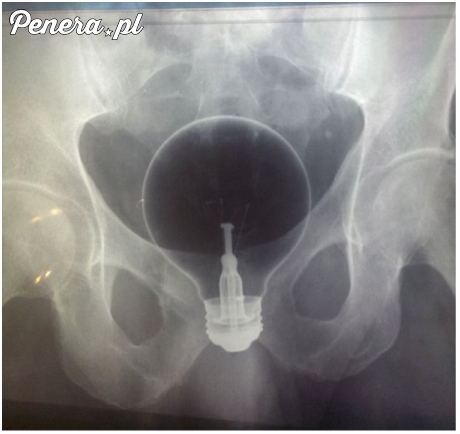

Świetny pomysł - w tyłku

To trzeba mieć talent